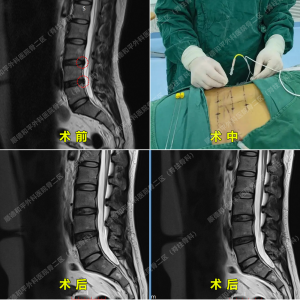

案例二:单侧双通道内镜技术(UBE)——精准解决复杂腰椎问题25岁陈嘉聪,因“陈旧性腰椎骨折”导致“腰痛伴右下肢放射性麻木半年余”,曾尝试多种保守治疗效果不佳。术前诊断显示L5/S1椎间盘脱出伴神经根病、椎管狭窄及退行性病变。张哉炯团队采用“单侧双通道内镜技术(UBE)”,通过双通道内镜精准定位,经皮椎间孔镜下完成髓核摘除术。

手术仅耗时1小时40分钟,术后第一天患者腰痛及下肢麻木明显减轻,住院4天后顺利出院。张哉炯主任同步指导术后康复锻炼,助力患者快速回归工作与生活。技术亮点:UBE技术创伤小、出血少,通过双通道扩大操作视野,适用于复杂椎间盘突出、椎管狭窄等病例,尤其适合年轻患者或需保留脊柱运动功能者。